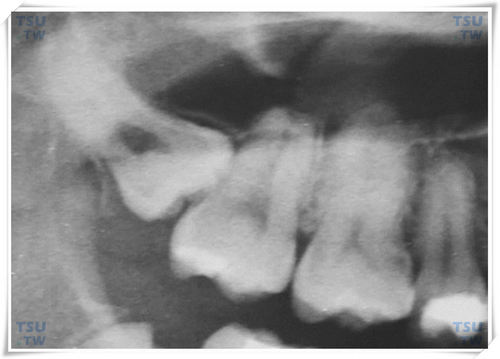

3倒逆是指上下颌智齿冠部向相反方向萌出生长的智齿,其智齿处在埋伏在颌骨内不能够萌出的状态。上颌倒逆阻生智齿是指智齿的咬合面朝向上方,见下图。上颌间位远中倾斜高位阻生智

8上颌垂直阻生智齿是指上颌智齿的咬合面垂直向下,智齿的中轴线与上第二磨牙中轴线近似平行,智齿的咬合面高于前牙的咬合面。 上颌垂直低位阻生智齿,是指阻生智齿的咬合面位于前